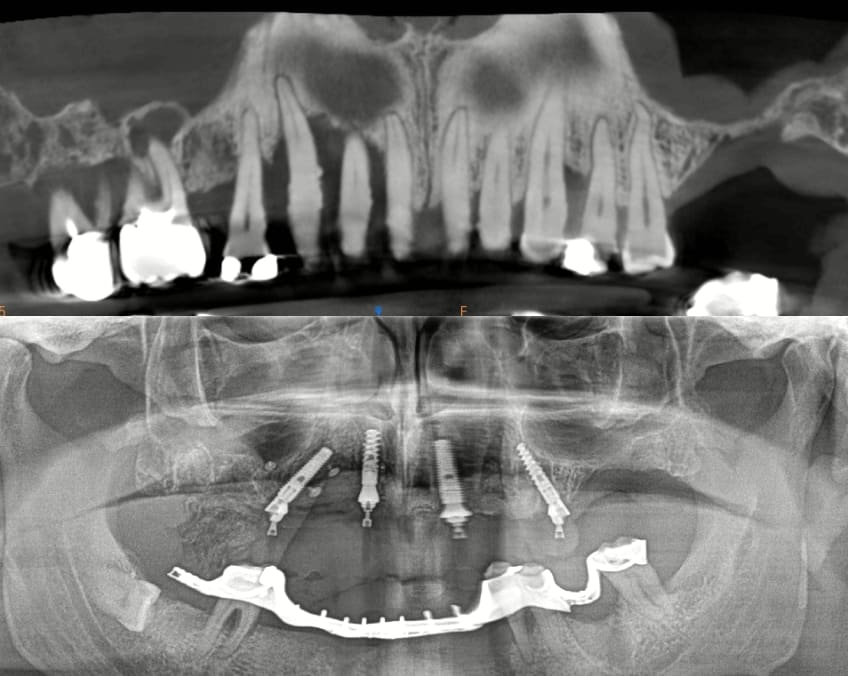

Mais celui la est tout chaud ( de vendredi dernier ) et j'ai regarder le temps que j'ai mis ( beaucoup plus complexe, donc plus long ). on va l'appeller Cas 2.

3 h de planif, modélisation du guide, puis 2 h environ pour la simulation de la chir , le modelisation et l'impression du bridge, qui tombe pile, zero retouche occlusale.

Avec un plan de traitement qui est suceptible de débat :)

Le cone beam prévu : all on 4 et 4 implants en bas qui seront posé dans 3 semaines.

Chir le vendredi matin. au vu de la possibilité de reculer pas mal les implants postérieurs, je trouvais qu'il y avait trop de porté entre les implants : je pars donc sur 6 implants.

Mais malgré les gros renforts, le guide résine n'est pas assez rigide : impossible de poser le bridge en immédiat. obligé de fraiser le bridge ( j'aurais du en prévoir un autre évidé, ce que je prévois pour lundi prochain ) et de mettre des piliers provisoires : 40 m de travail de labo en plus..